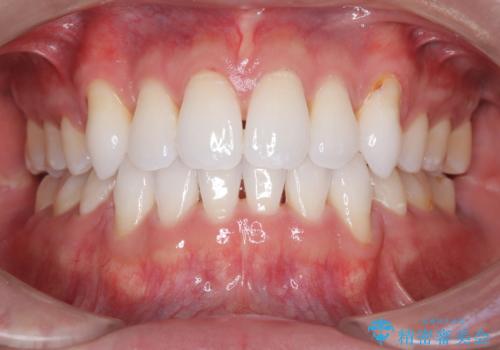

欠けやすい大きなプラスチック充填から、耐久性の高いセラミッククラウンへ

担当医 河口智英